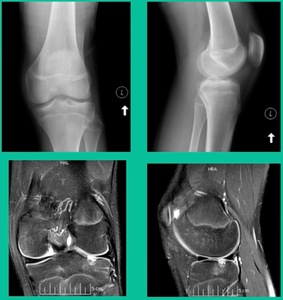

Now a couple of quick cases. This is juvenile OCD. This is the first series of three or four, just juveniles. 14-year-old, intermittent knee pain, lateral femoral condyle OCD (Figure 1).

This is an 11-year-old. Left knee lateral knee pain. Effusions, the same type of classic findings (Figure 3)

The challenge is this. This series of patients were populated by early decisions to treat when patients don’t have symptoms. That’s a problem in my mind. Post-Op, they protect their weight-bearing. That’s actually treatment. These are often smaller lesions of the medial femoral condyle. They do really well. That being said, it’s an option. It’s not my option. My option for someone who’s macroscopically unstable is we use biocomposite screws (Figure 4).